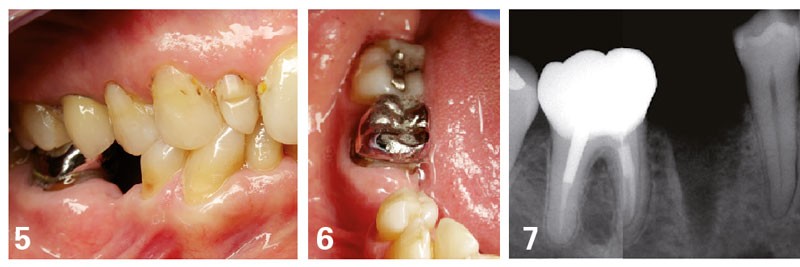

Dans le cas exposé figures 5 à 7, le traitement prothétique proposé pour remplacer la 45 peut être la couronne sur implant ou le bridge traditionnel 44-[45]-46. Cette dernière solution est moins favorable, sur le plan de la conservation tissulaire, que la solution implantaire. Le devoir de conseil du chirurgien-dentiste va donc naturellement l’amener à conseiller le patient en faveur de cette solution implantaire (tableau 2).

Dans le cas où une contre-indication formelle interdit le recours à l’implant (affection systémique, par exemple), la solution du bridge peut être proposée.

Le raisonnement suit alors l’exemple précédent, avec une possibilité pour le bridge métallique : une préparation a minima (économie tissulaire de 44) et, surtout, la volonté du patient satisfait de la présence de la couronne métallique sur 46 sans aucune complication.